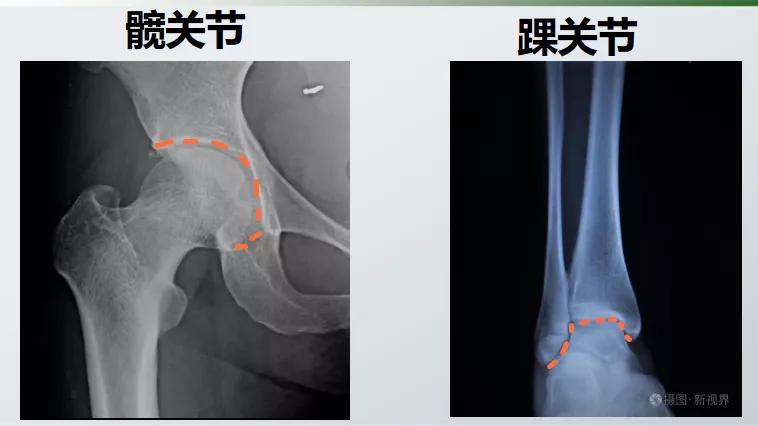

髋关节和踝关节都是半包围结构

相互嵌合,其骨头的稳定性好

而膝关节几乎就是两个平面贴在一起

单靠骨头几乎没有稳定性